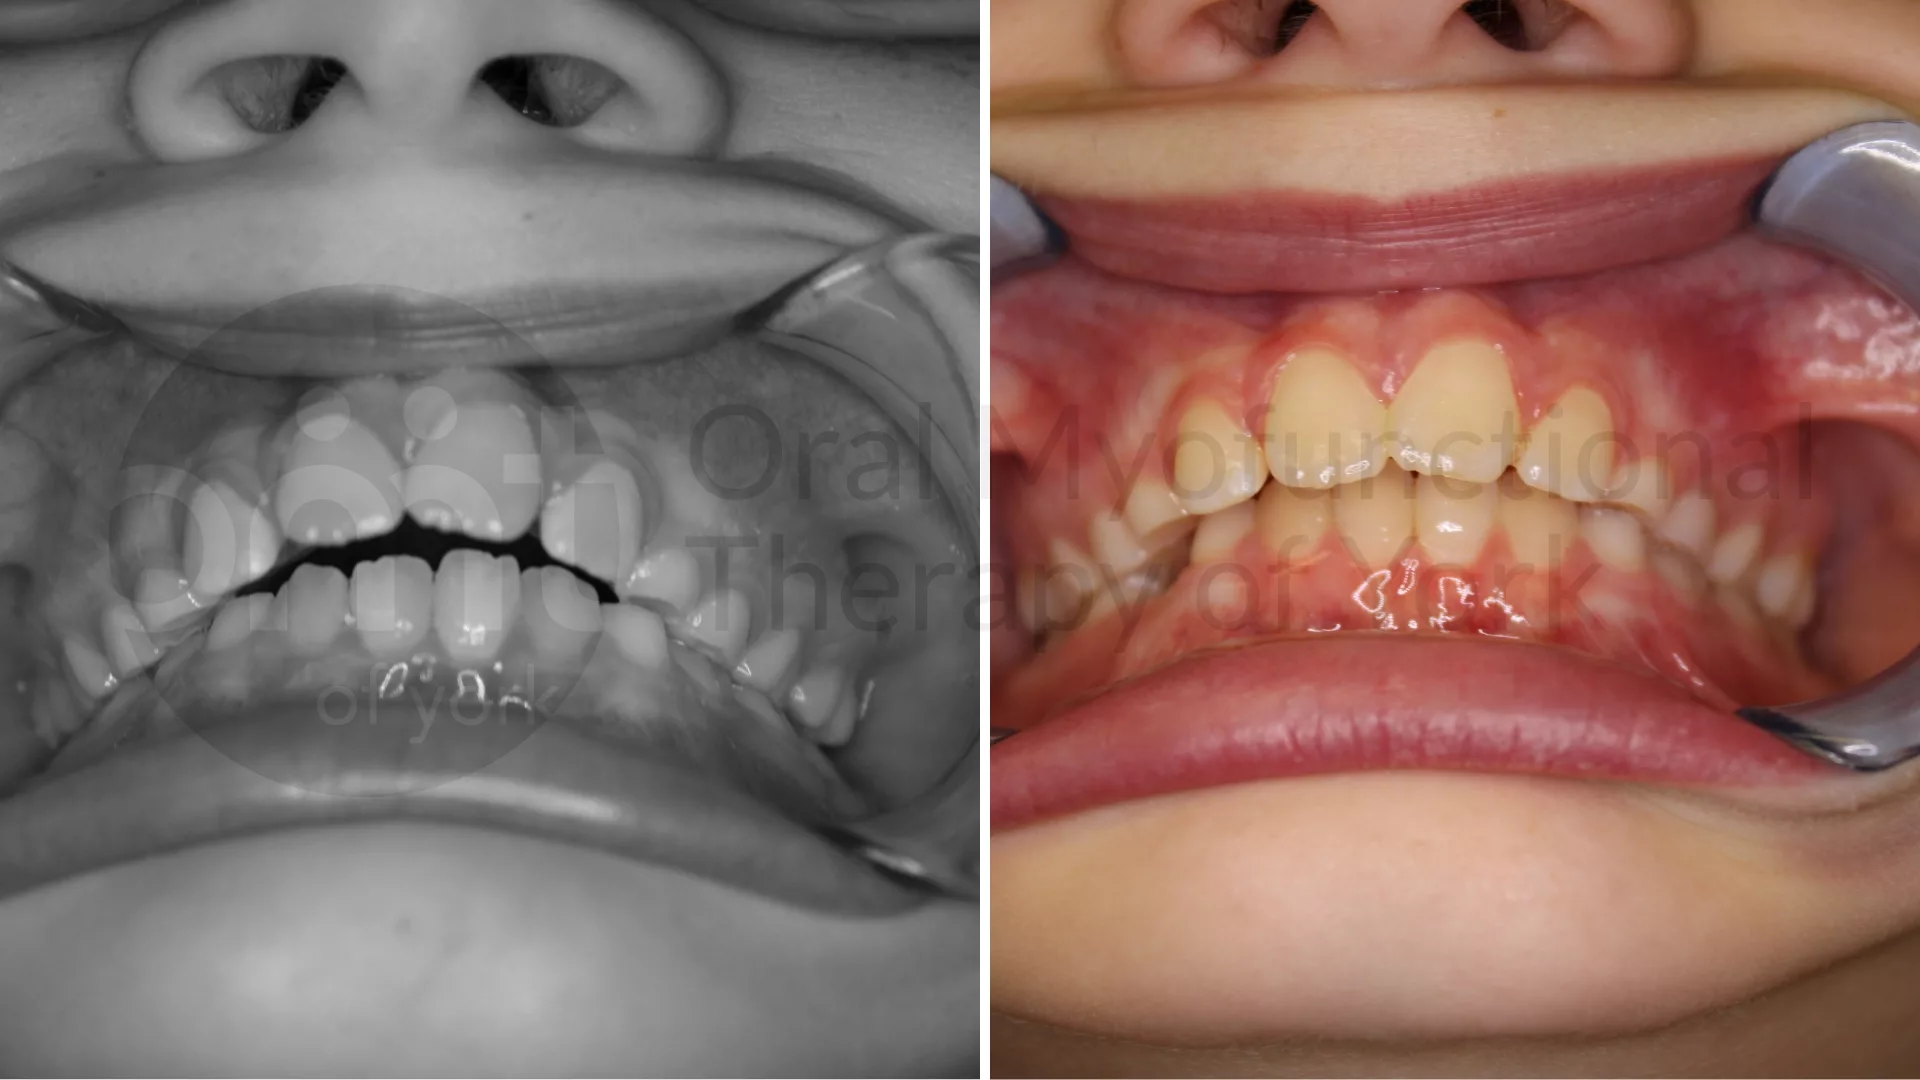

Teaching the tongue to rest again the hard palate leads to better alignment  of the front teeth and allows the open bite to close.

Thumb sucking elimination, therapy and a frenectomy leading to improved growth patterns

Eliminating oral habits such as thumb sucking can lead to better alignment of the teeth and jaws.